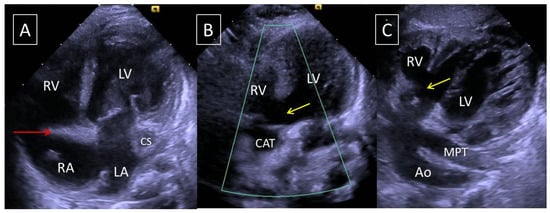

3.5. Case Report

| 39 (patient) | Tricuspid atresia | Large outlet | 1 | 3 | Left | LSCV to CS |